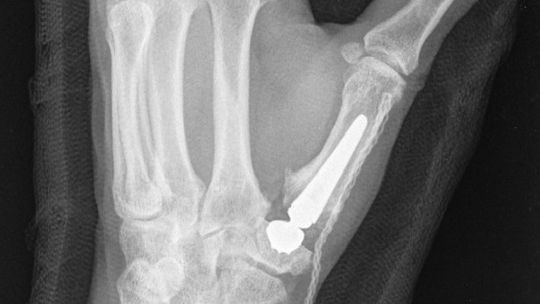

Na czym polega zabieg?

Staw zastępowany jest endoprotezą, co pozwala:

Dzięki nowoczesnej technice i implantom Touch CMC I pełna ruchomość ręki wraca już po ok. 6 tygodniach!

Proteza jest dwumobilna, co oznacza, że: zapewnia naturalny ruch w dwóch miejscach, gwarantuje pełną stabilność i minimalizuje ryzyko zwichnięcia.